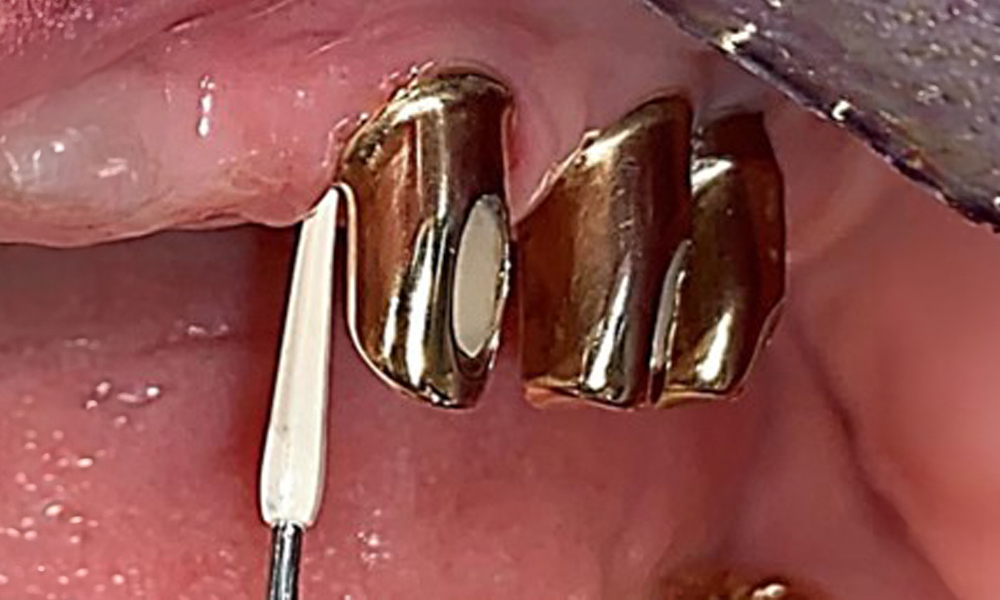

Probing implant 23 at a probing depth of 4 mm using a plastic probe, showing negative BOP findings and a hyperplastic papilla.

Fig. 6: Probing implant 23 at a probing depth of 4 mm using a plastic probe, showing negative BOP findings and a hyperplastic papilla.

The periodontal status should be thoroughly examined once a year. This examination provides comprehensive documentation of the periodontal and implant findings, including pocket depths, periodontal recession and furcation involvement. This will ensure a rapid response to any potential progression of the mucositis, gingivitis, periodontitis or peri-implantitis. Implant probing using a plastic probe is recommended. In the present case, a mesial probing depth of 4 mm was detected mesial to implant 23. No suppuration or bleeding was detected, indicating the absence of peri-implantitis.

The periodontal condition remains stable. There was no gingival or peri-implant soft tissue inflammation. At 1 to 3 mm, the probing depths were within the physiological range. There are generalised recessions measuring 1 to 3 mm. Implant 23 has an increased probing depth of 4 mm, although there are no signs of secretion or bleeding (Fig. 6). The total BOP is 12%.